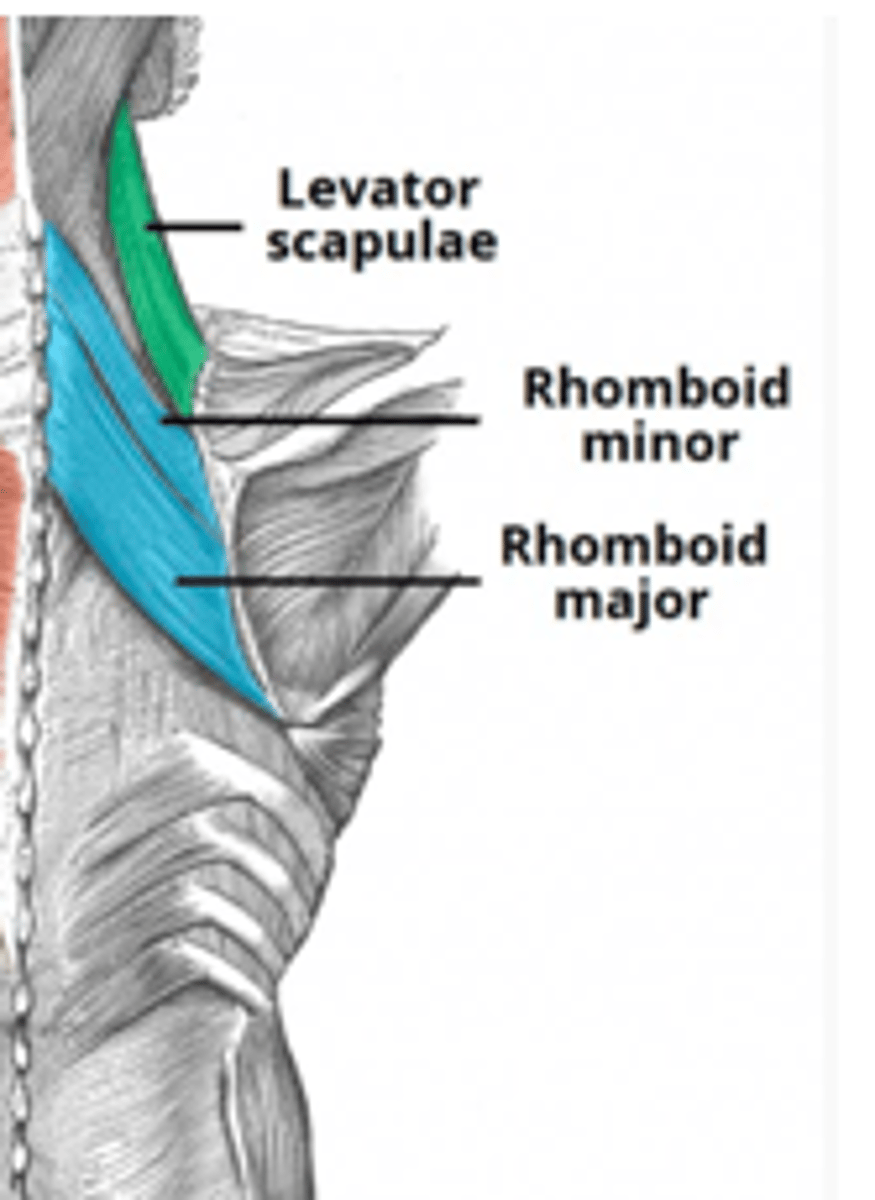

(Posterior axioappendicular and scapulohumeral muscles:) Deep posterior axioappendicular muscles (extrinsic shoulder)

Levator Scapulae and Rhomboid minor and major

(Deep posterior axioappendicular muscles (extrinsic shoulder):) Levator Scapulae

-Elevates and rotates scapula

-Dorsal scapular n. (C5)

(Deep posterior axioappendicular muscles (extrinsic shoulder):) Rhomboid Minor and Major

-Retract and rotates scapula

-Dorsal scapular n. (C5)